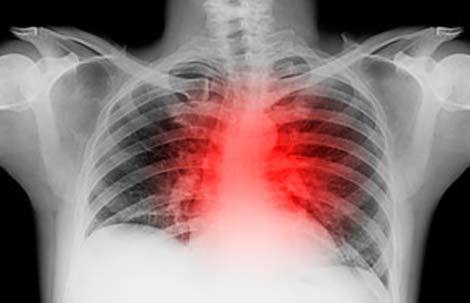

7. Xét nghiệm máu phát hiện sớm cơn đau tim

Một cơn đau tim bắt đầu với hàng loạt tắc nghẽn trong các mạch máu, do đó còn nơi nào tốt hơn để tìm kiếm chẩn đoán về các vấn đề về tim mạch tốt hơn trong máu? Hiện tại, cách đáng tin cậy nhất để kiểm tra tình trạng các mạch của tim là dùng phương pháp chụp động mạch, một thủ thuật can thiệp bao gồm việc lượn một ống nhỏ vào các mạch máu từ một động mạch ở chân. Tuy nhiên, các nhà nghiên cứu hiện đã xác định được một bảng sơ bộ gồm 23 gen mã hóa các protein trong máu, đạt 83% độ chính xác trong việc phát hiện những tắc nghẽn mạch máu điển hình của bệnh tim. Khi các bác sĩ thêm xét nghiệm máu này vào những biện pháp đo lường nguy cơ đau tim hiện có, kể cả các triệu chứng đau ngực và tiền sử vấn đề sức khỏe của gia đình, nó đã nâng khả năng phân loại bệnh nhân có nguy cơ cao hay thấp của họ thêm 16% so với việc chỉ sử dụng những phương pháp truyền thống. Quá nhiều khi hy vọng rằng, mình các xét nghiệm máu có thể dự đoán cơn đau tim, ít nhất là trong hiện tại, nhưng biện pháp này có thể đóng vai trò như một kêu gọi cảnh báo sớm cho những bệnh nhân có nguy cơ cao. Việc thúc đẩy các thay đổi trong thói quen ăn uống và lối sống ở những bệnh nhân này có thể giúp họ ngăn chặn nguy cơ bị đau tim.